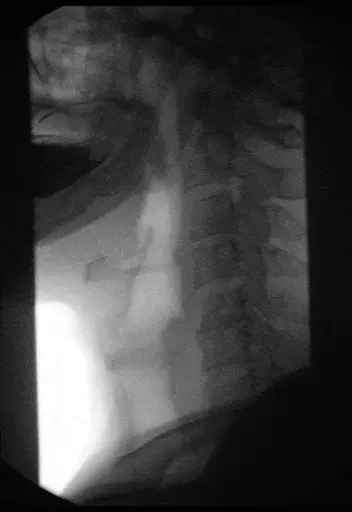

GIF - Barium swallow showing a normal swallowing reflex

Creative commons source by Hellerhoff, modified by Anka Friedrich [CC BY-SA 4.0 (https://creativecommons.org/licenses/by-sa/4.0)]